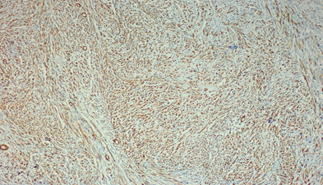

Introduction: Colorectal cancer (CRC) is one of the most common cancers worldwide. Individuals with elevated lipid levels are at risk for developing cardiovascular disease as well as cancer. Sterol regulatory element-binding protein transcription factors (SREBPs) are inducers of lipid synthesis. It’s reported that SREBP1a and its target gene FASN are metabolic oncogenes. Their suppression leads to decrease lipogenesis and reduce proliferation and survival of CRC. This study focuses on the expression of SREBP1a and FASN proteins in colorectal adenoma and carcinoma and correlates their expression with the available clinicopathological data.

To citation of this article: Dr. Aya Abuzeid, Egypt,Role of sterol regulatory element-binding protein 1a and fatty acid synthase in colorectal carcinoma, Global Journal of Pathology & Laboratory Medicine